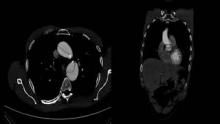

Optimal treatment of the acute type A dissection is still controversial. The current guidelines give indistinct recommendations about which surgical valve-sparing procedure should be performed when aortic dissection occurs and which method of cannulation should be used for appropriate antegrade perfusion. Cannulation of the innominate artery has been a perfect alternative for 20 years, including in patients with acute type A aortic dissection (1). However, the published data contain fewer reports about this approach than about axillary or femoral cannulation. Compared with axillary or femoral artery cannulation, innominate artery cannulation has several advantages: absence of the need for a second incision, higher flow rate, and antegrade cerebral perfusion (2, 3). Today, aortic valve reimplantation technique is performed relatively rarely (<10%) in patients with acute type A aortic dissection (4). This type of surgery requires higher surgical skills and is used with caution in this category of patients. Here, the authors present innominate artery cannulation and modified reimplantation of tricuspid aortic valve in a young man with type I DeBakey acute aortic dissection (5, 6). Postoperative echocardiography one year later after surgery showed a satisfactory result of the procedure with good aortic valve function. Coaptation zone of the reimplanted valve was type A according to Pethig classification (7).